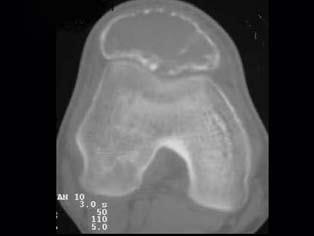

问题 患者,男性,30岁,近2年来感右膝疼痛,活动后加重,2周前由于剧烈运动后,右膝活动受限,右膝压痛明显,有波动感,皮肤稍显红肿,以髌骨部明显,请结合所提供图像,选择最佳选项 ( )

选项 A、骨巨细胞瘤 B、动脉瘤样骨囊肿 C、非骨化性纤维瘤 D、骨囊肿 E、纤维性骨皮质缺损

答案 B